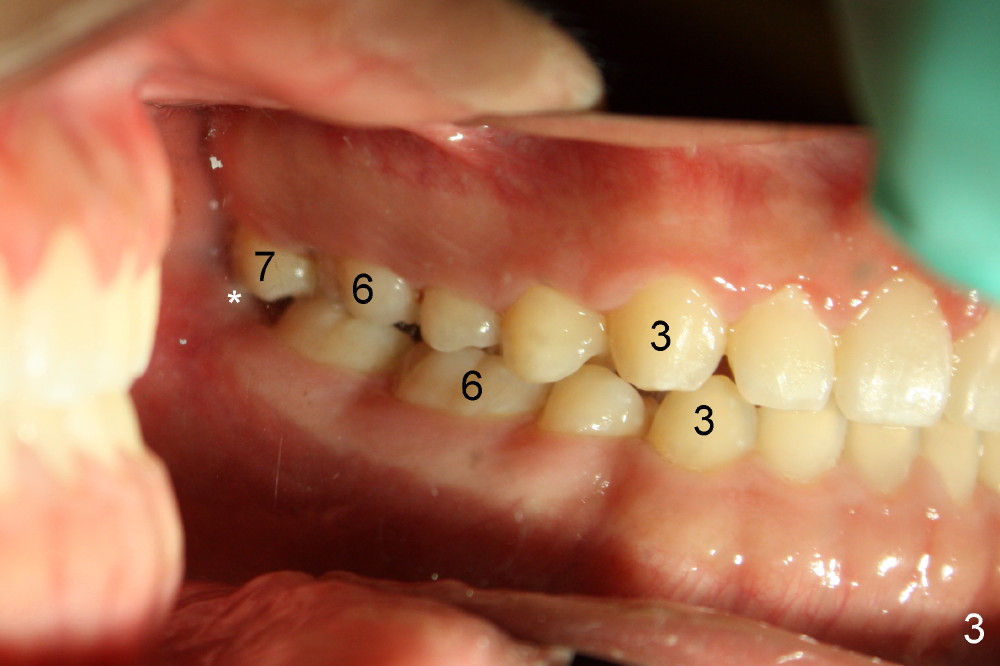

打完下颌神经麻药,乘麻药还没有奏效,拍摄图二至图五,图二,图三显示前牙第一类咬合,而后牙第三类,上颌第二磨牙(7)咬在下颌牙龈(*,仿佛形成白斑(leukoplakia))。图四,图五显示上颌第二磨牙向下伸长。那时我还不具有力挽狂澜能力。那么这四个智齿该拔吗?